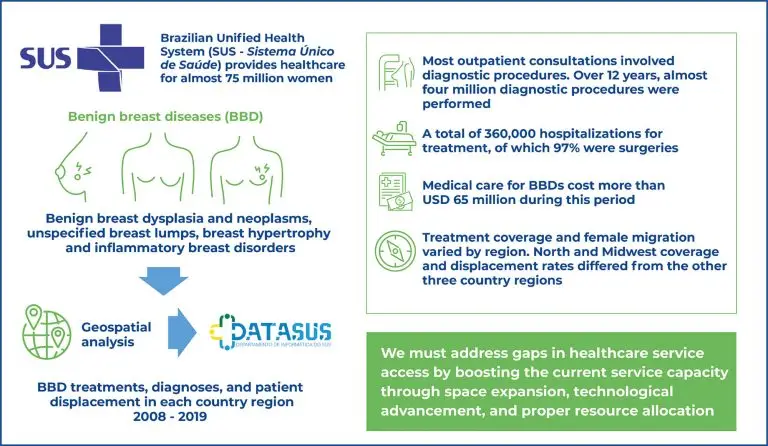

28/Mar/2025

Brazil’s benign breast disease care profile and geospatial analysis

DOI: 10.31744/einstein_journal/2025AO1132

Highlights ■ Most outpatient consultations comprised diagnostic procedures. ■ In the past 12 years, medical care for benign breast diseases has cost >USD 65 million. ■ Women from North and Midwest Brazil had higher diagnosis and treatment displacement rates. ABSTRACT Objective: To quantitatively and geospatially analyze coverage and displacement for the diagnosis and treatment of benign breast diseases in the Brazilian Unified Health System between 2008 and 2019. Methods: Datasets from the Brazilian Ministry of Health were used to survey […]

Keywords: Brazil; Breast diseases; Breast neoplasms; Demography; Epidemiology; Health expenditures; Healthcare costs; Hospitalization; Incidence; Primary healthcare; Public health; Strategy planning; Unified Health System